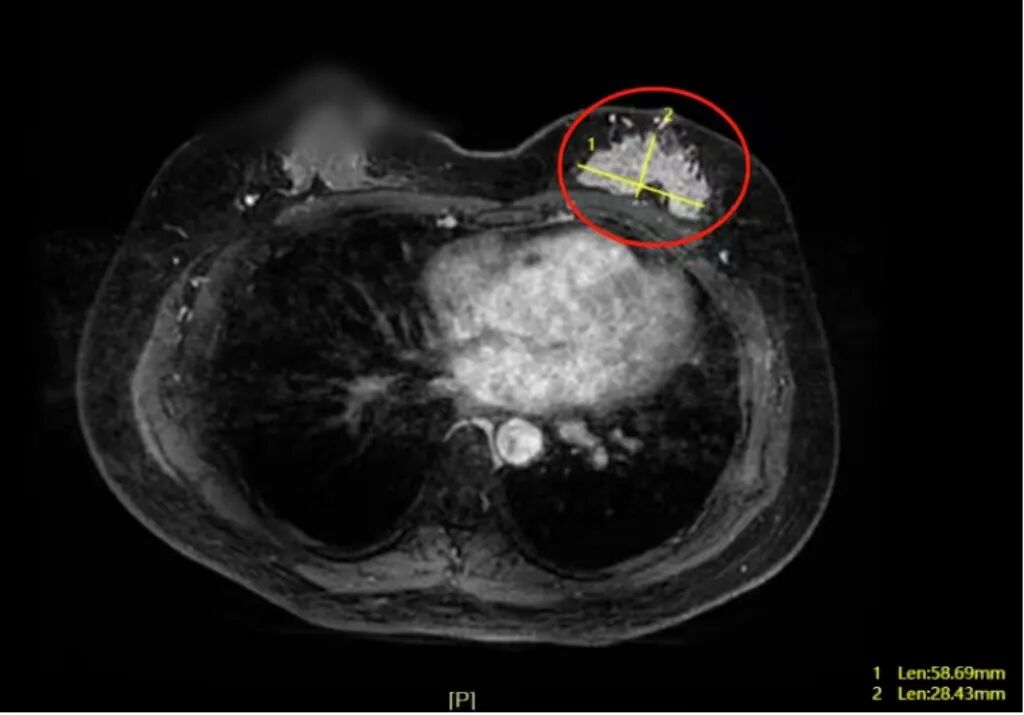

两年前,宋女士就查出自己有3类乳腺结节,但因心存侥幸,既没坚持乳房自检,也未按时做年度B超体检。2025年的一天,她在洗澡时摸到乳房内的大肿块,才猛然警惕就医。省二医胸壁外科研究所乳腺甲状腺专科副主任医师赖勇强博士团队接诊宋女士后,为她进行了详细体检和相关检查。检查结果显示:宋女士左侧乳房有一个大小约5cm×5cm×2.5cm的肿块,磁共振结果高度怀疑是乳腺癌,并通过穿刺活检最终确诊了癌症的判断。

△磁共振检查显示,宋女士的左侧乳房有一个大小约5cm×5cm×2.5cm的肿块